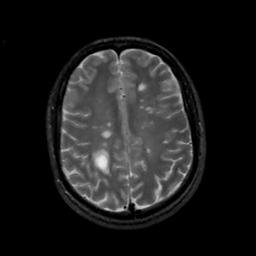

MR Study #6, March 17, 1991 -- Slice #35

[Home][Help][Clinical][Tour 1][Tour 2] Slice 35